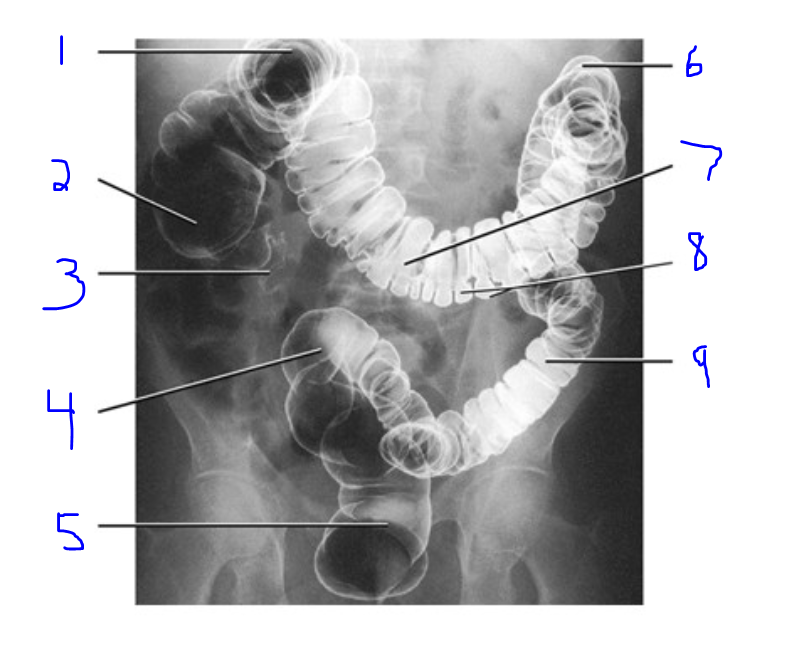

Label

Right Colic Flexure

Cecum

Vermiform appendix

Sigmoid colon

Rectum

Left Colic Flexure

Transverse Colon

Haustra of Colon

Descending Colon

Describe which contain air and barium.

Supine

Barium (ascending/descending/rectum)

Air (transverse/sigmoid)

Prone

Barium (transverse/sigmoid)

Air (ascending/descending/rectum)